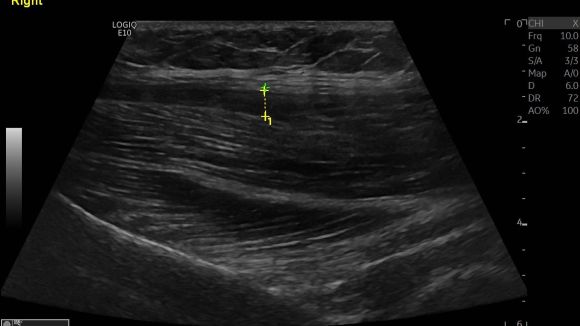

We did an ultrasound and detected a partial tear in the upper proximal part of the fascia to the gluteus medius. You can see the different echogenicity between the right and left pictures.  The hypoechoic area and the thickness of the fascia show the partial tear.

Don’t forget that partial tear can also be found in the upper proximal gluteal are to the ilium and not always in the trochanter area.